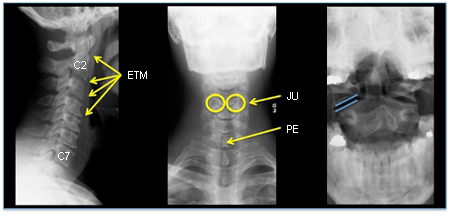

[Figure caption and citation for the preceding image starts]: Padrões de fratura comuns com trauma grave da coluna cervical. Acima: imagem de tomografia computadorizada axial mostrando uma fratura cervical no nível C5. Parte inferior: tomografia computadorizada axial mostrando luxação da fratura no nível C6-C7.Do acervo pessoal de Michael G. Fehlings [Citation ends].

[Figure caption and citation for the preceding image starts]: Padrões de fratura comuns com trauma grave da coluna cervical. Linha superior: fratura cervical do tipo explosão no nível de C5. Canto superior esquerdo: imagem axial de tomografia computadorizada mostrando uma fratura do corpo vertebral C5. Canto superior direito: ressonância magnética ponderada em T2 do sagital médio mostrando retropulsão do corpo de C5 com compressão da medula espinhal, alterações do sinal ponderado em T2 na medula espinhal e alterações do sinal ponderado em T2 no complexo ligamentar posterior, indicando ruptura desses ligamentos. Linha inferior: fratura-luxação no nível de C6-C7. Canto inferior esquerdo: tomografia computadorizada axial até o nível da faceta C6/C7. Embaixo à direita: ressonância magnética sagital média ponderada em T2 demonstrando compressão da medula espinhal e alteração do sinal ponderado em T2 na medula espinhalDa coleção pessoal de Michael G. Fehlings. [Citation ends].